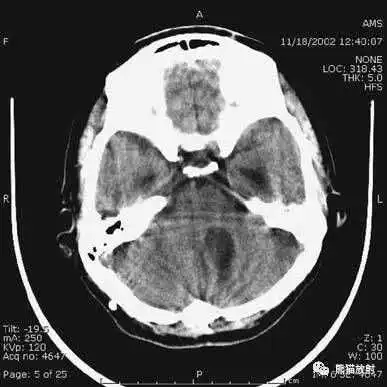

动脉瘤破裂导致蛛网膜下腔出血、

脑室积血、非交通性脑积水。

与外伤性蛛网膜下腔出血不同,动脉瘤破裂导致的SAH常不累及大脑凸面,而位于基底池附近。脑动脉瘤常位于鞍上池的Willis环血管。

A:四脑室积血;

B:中脑导水管、环池、右侧侧脑室颞角积血,前交通动脉处(动脉瘤好发位置)出血密度较高;

C:三脑室积血;

D-F:侧脑室积血,蛛网膜下腔出血(血液代替了脑脊液)。